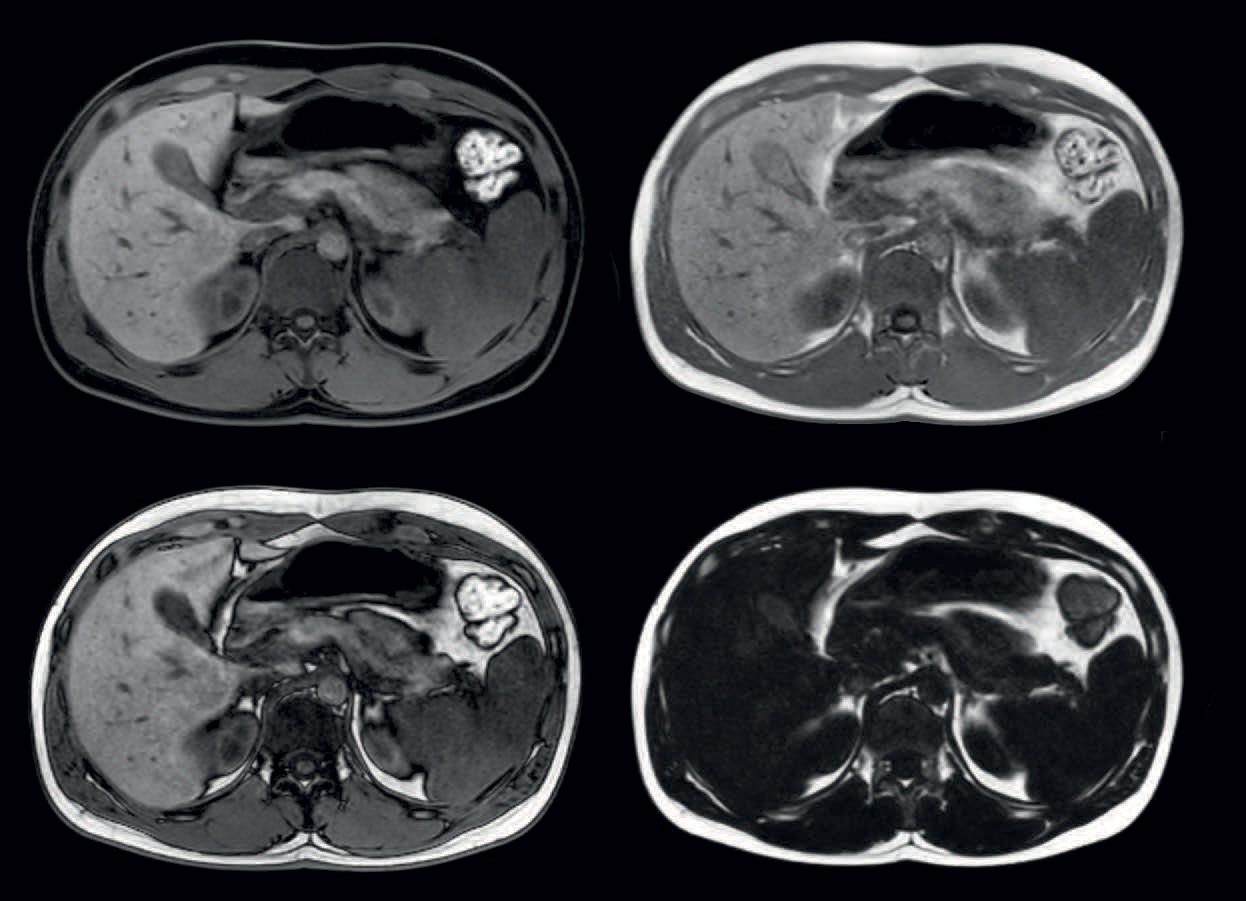

mDIXON provides four different contrasts in one scan: water, fat, in-phase and out-phase images. Voxels 1.3 x 1.5 x 2.5 mm, high dS SENSE acceleration factor, breathhold 16 seconds.